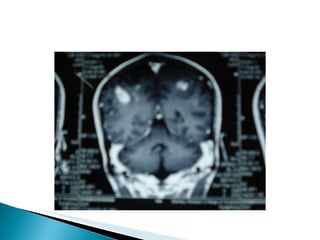

Bilateral fronto-parietal hemorrhagic infarct Filling defect noted in SSS- suggeting SSS thrombosis . Final Diagnosis: Dural Venous Sinus thrombosis

Rpt CT scan(12.8.09):ICH with midline shift(CT report Not available) Rpt CT scan(22.8) :Lt. parieto-occipital hemorrhagic infarct  MRI and MRV(22.8) : Lt. fronto parietal hemorrhagic infarct -Rt.tranverse, Rt.sigmoid and SSS thrombosis

Bilateral fronto-parietal hemorrhagicinfarct Filling defect noted in SSS- suggeting SSS thrombosis . Final Diagnosis: Dural Venous Sinus thrombosis

Rpt CT scan(12.8.09):ICHwith midline shift(CT report Not available) Rpt CT scan(22.8) :Lt. parieto-occipital hemorrhagic infarct MRI and MRV(22.8) : Lt. fronto parietal hemorrhagic infarct -Rt.tranverse, Rt.sigmoid and SSS thrombosis

Combination of noncontrast MRI and MRA and MRV : best method for the diagnosis and follow up of CVT . MRI/V -Early: absence of flow void & isointense on T1 for occluded vessel; Hypo intense on T2 Late: hyper intense thrombus on T1 & T2